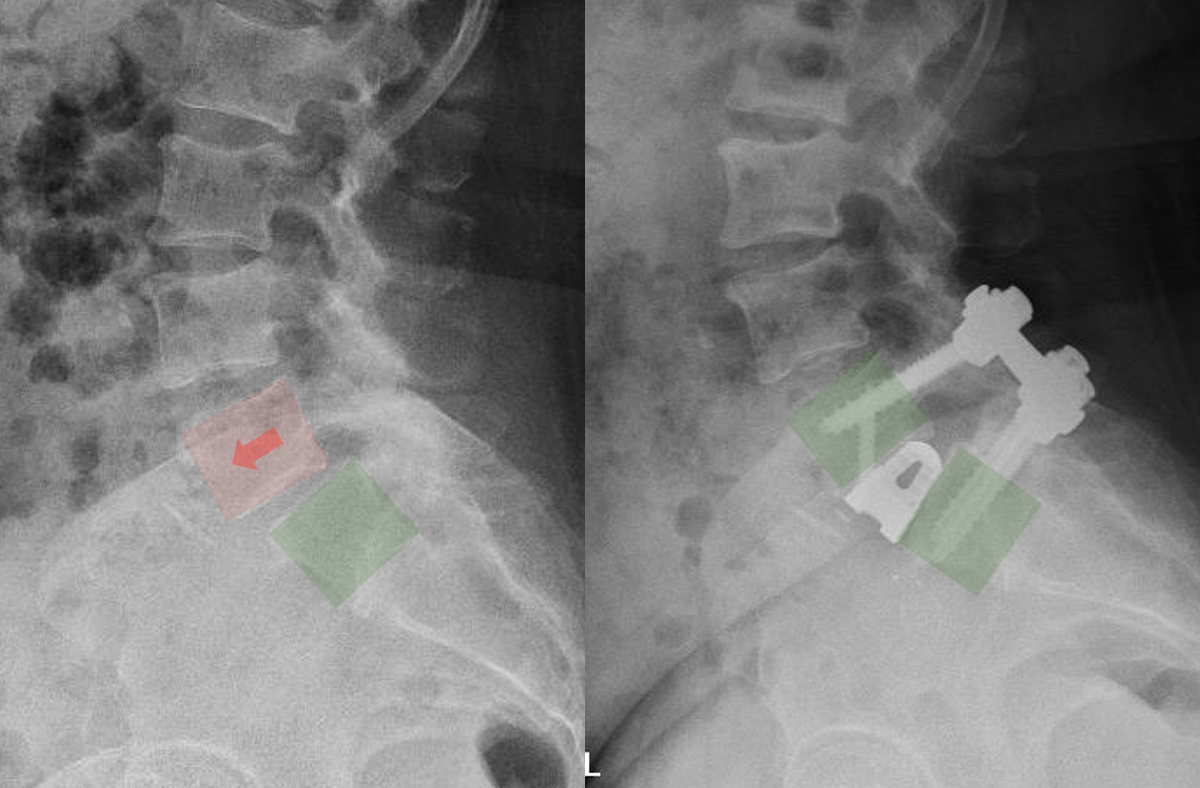

Diagram of lumbar spine showing a spinal fusion surgery with metal plates and screws.

X-ray images of the lower spine showing a surgical procedure with hardware, such as screws and rods, implanted in the lumbar vertebrae.